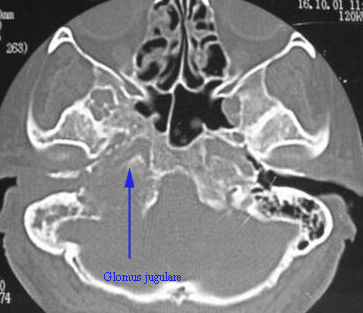

CT scan image of a patient with Glomus jugulare

Investigations: Radiological investigations help in the diagnosis.

CT scan and Contrast MRI using Gadolinum enhancement is very helpful in delineating tumor extension.